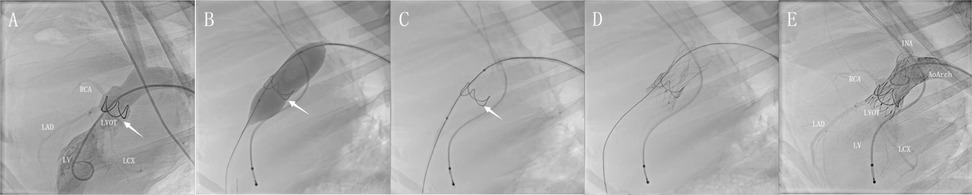

Background: Transcatheter aortic valve implantation (TAVI) has gained widespread clinical acceptance owing to its minimally invasive approach and enhanced postoperative recovery. This study developed a standardized ovine aortic stenosis (AS) model through surgical implantation of a circular bioengineered annular stent in the aortic root, creating a reproducible pathomimetic platform for TAVI evaluation. Following hemodynamic stabilization, TAVI procedures were performed to systematically assess mid-to-long-term valve functionality and calcification progression. Methods: AS model was established in 11 sheep using extracorporeal circulation assistance technology. Following hemodynamic stabilization (2-4 weeks), TAVI was performed. The modeled sheep were divided into two groups to monitor valve conditions at 3 months (n=6) and 6 months (n=5), respectively. Additionally, a non-modeled control group was established, with valve conditions assessed at 3 months (n=2) and 6 months (n=1). Preoperative ultrasound data, collected on the day of TAVI, which served as the baseline. Key hemodynamic parameters including blood flow velocity, transvalvular pressure gradient, and left ventricular ejection fraction were measured at 30, 90, and 180 days postoperatively, in accordance with Valve Academic Research Consortium-3 (VARC-3), to evaluate temporal changes in hemodynamics. The effects of the AS model on valve function were further analyzed by integrating final histopathological findings and calcification degree outcomes. Results: Successful AS model establishment was achieved in all 11 sheep, with significant increases in mean transvalvular pressure gradient (Δ+17.98±12.71 mmHg) and peak flow velocity observed post-modeling (Δ+ 2.23±0.38m/s). Post-TAVI evaluation demonstrated progressive hemodynamic normalization, achieving pre-modeling levels (1.72 vs 6.91 mmHg, P=0.058/ 0.80 vs 1.51 m/s, P=0.065) at 180-day follow-up. LVEF remained stable throughout the experimental period. Histopathological analysis indicated comparable calcification burden between 90 and 180 days (Calcium Content: P=0.7459 and Calcification Score: P=0.5455). Conclusions: The surgically induced ovine AS model effectively replicates clinically relevant hemodynamic perturbations while maintaining excellent procedural feasibility. TAVI in this model achieves complete hemodynamic normalization without accelerating bioprosthetic valve degeneration or calcification. This standardized preclinical platform enables rigorous evaluation of TAVI device performance and durability, providing robust scientific validation for translational applications.